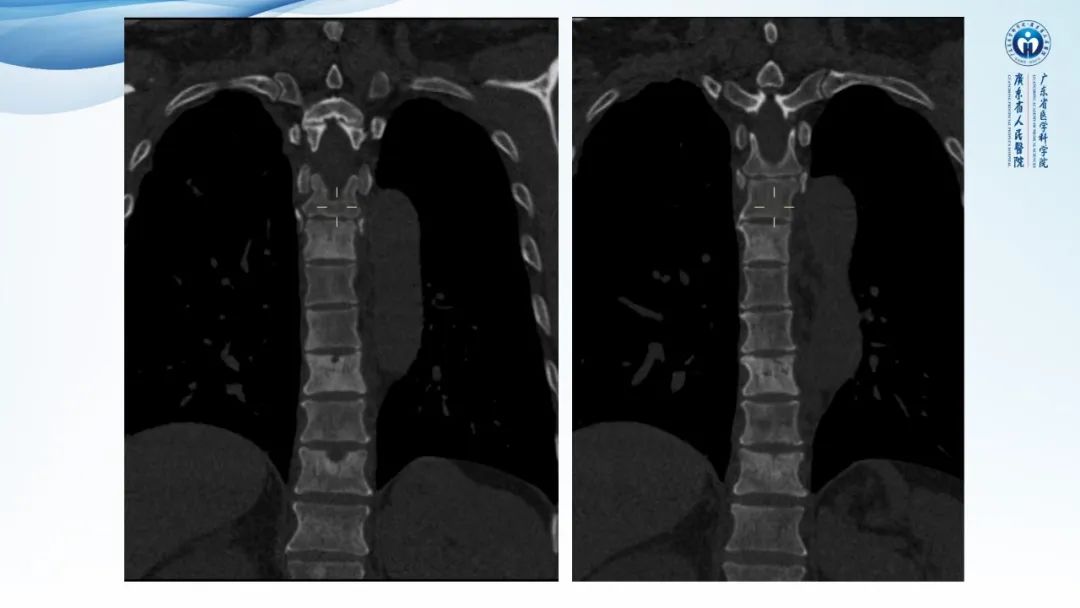

一例表现为弥漫中轴骨骨质增生硬化病变讨论

• 中轴骨多发成骨为主病灶-POEMS综合征/硬化性骨髓瘤

• 慢性骨髓炎(非结核分支杆菌)、SAPHO综合征 待排除